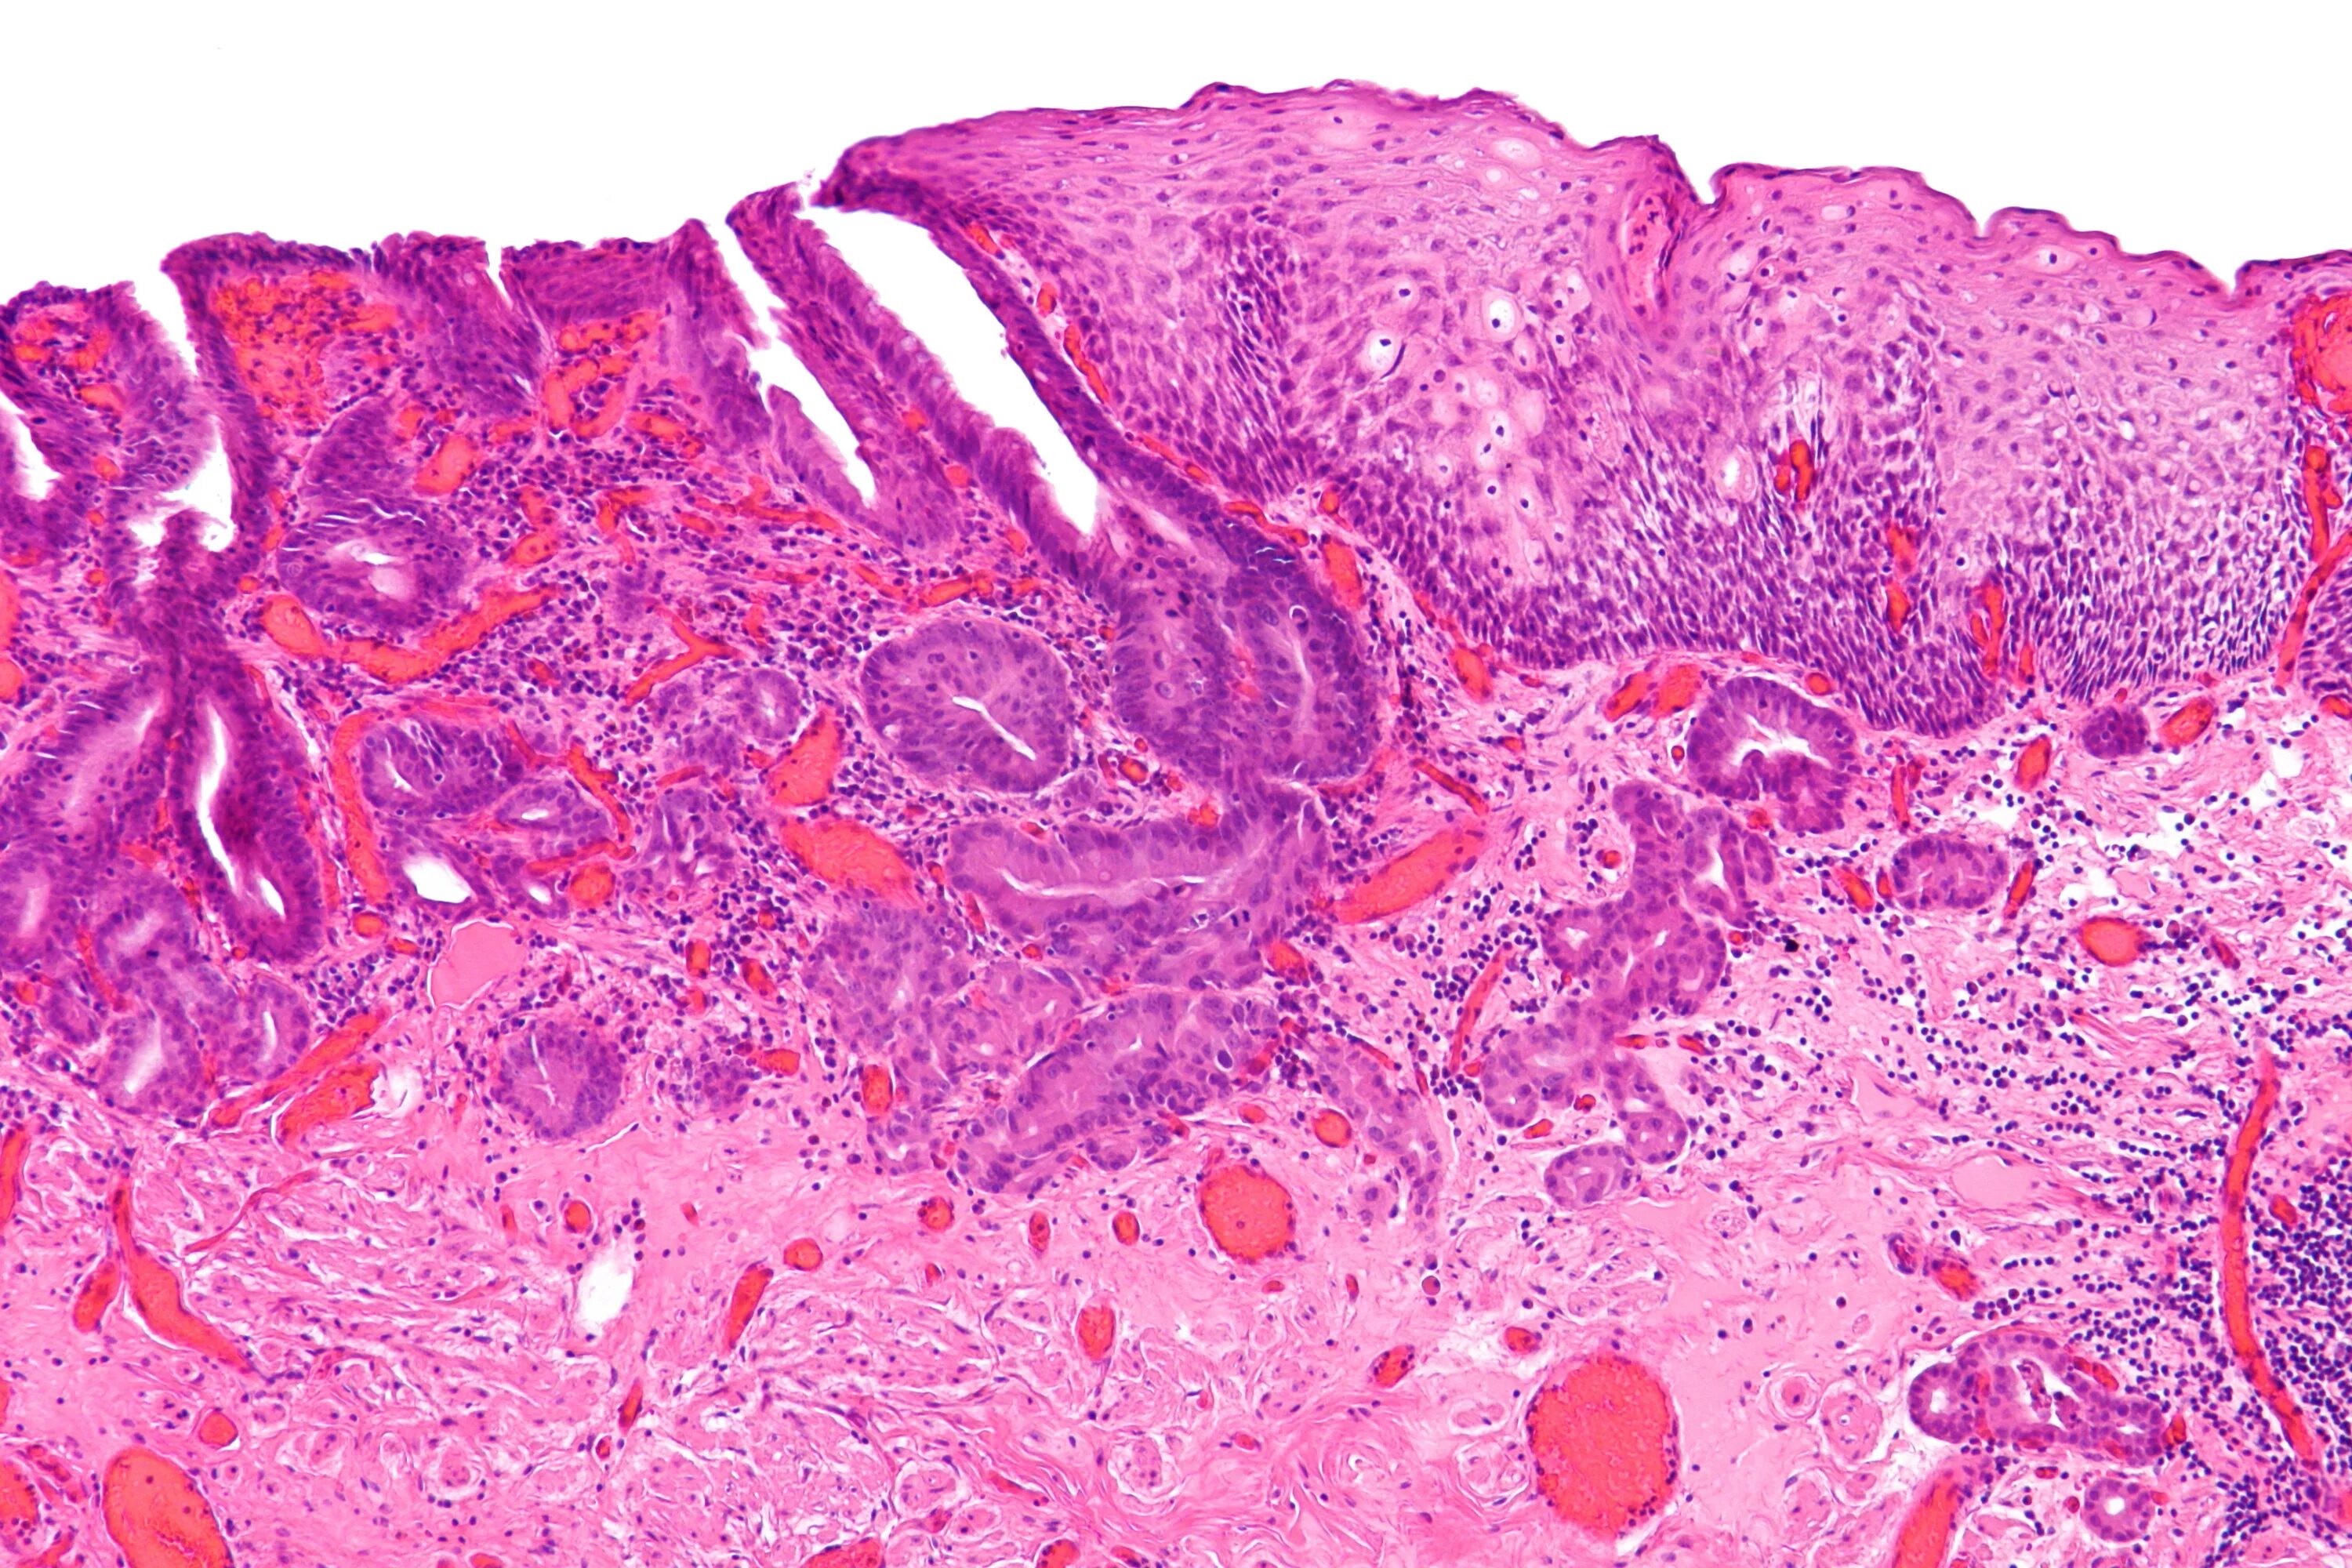

Гистологическое исследование слизистой